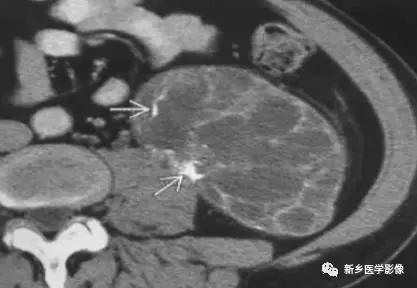

13

肾脏肿瘤

主要包括合并钙化的常见肿瘤或肿瘤样病变,如:肾囊肿,肾细胞癌,多房囊性肾瘤,多囊肝多囊肾囊壁钙化,肾脏结核,肾脏钙乳症